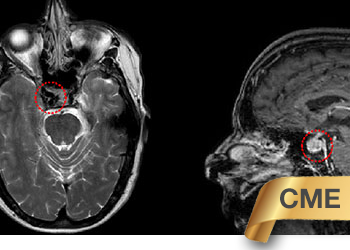

Endovascular:

CME:

Symptomatic Near-Occlusion of the Carotid Artery

Author: Jonathan L. Brisman M.D., F.A.C.S., Read More!

Right Vertebral Artery Compression Syndrome

Author: Artem Y. Vaynman M.D., F.A.A.N.S., F.A.C.S., Read More!

Direct Carotid Cavernous Fistula (CCF)